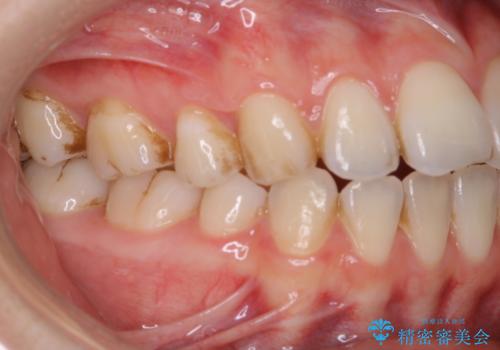

1年ぶりにPMTCで歯の着色落とし

- しばらく歯科医院へ行けなかったため、しっかり着色や汚れを落として欲しいとのことで来院されました。全体的に着色や歯石が付着していたためPMTC60分コースを行いました。